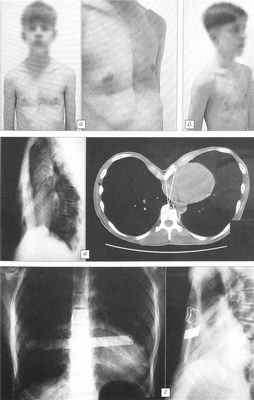

Пример 2. Больной Л., 36 лет, диагноз: воронкообразная деформация грудной клетки III степени. Произведена торакопластика по модифицированной методике Salamaa—Paltia. При выполнении операции явного повреждения плевры не отмечено, поэтому дренирование плевральной полости не осуществлялось. При ультразвуковом исследовании в 1-е сутки после операции определялось около 100 мл жидкости в правой плевральной полости. Произведена пункция, получено 70 мл геморрагического содержимого. В последующие дни течение послеоперационного периода без осложнений. На 7-е сутки пациент вертикализирован, разрешено ходить. На 9-е сутки появились одышка, слабость, субфебрильная температура. Аускультативно определялось резкое ослабление дыхания справа, притупление перкуторного звука в нижних отделах грудной клетки, на обзорной рентгенограмме грудной клетки — уровень жидкости в правой плевральной полости. Произведена пункция плевральной полости, удалено 900 мл геморрагического содержимого. Через 4 дня — повторная плевральная пункция, получено 400 мл более светлой геморрагической жидкости. Проводились противовоспалительная терапия, дыхательная гимнастика. Скопления жидкости в плевральных полостях не отмечалось. На 20-е сутки пациент выписан из стационара в удовлетворительном состоянии. Через 6 мес удалена пластина Paltia. При осмотре через 1 год жалоб не предъявляет, каркас грудной клетки сформирован правильно (рис. 2).

Рис. 2. Больной Л. 36 лет. Воронкообразная деформация грудной клетки III степени.a — до оперативного лечения, б — через 1 год после торакопластики.

Пример 3. Больной П., 16 лет, диагноз: воронкообразная деформация грудной клетки III степени. При поступлении жалобы на одышку после незначительной физической нагрузки, периодические боли за грудиной. На ЭКГ отмечается перегрузка правых отделов сердца, блокада правой ножки пучка Гисса, при исследовании функции внешнего дыхания — снижение функциональной остаточной емкости легких на 30%. Произведена торакопластика по модифицированной методике Salamaa—Paltia. В послеоперационном периоде проводилось активное дренирование правой плевральной полости в течение 2 сут. Получено 450 мл геморрагического отделяемого. Дальнейшее течение послеоперационного периода без осложнений. Через 6 мес удалена пластина Paltia. Результат лечения хороший, каркас грудной клетки сформирован правильно. При осмотре через 2 года: каркас грудной клетки сформирован правильно, на фоне роста (пациент вырос на 15 см) рецидива деформации нет (рис. 3).

Рис. 3. Больной П. 16 лет. Воронкообразная деформация грудной клетки III степени, асимметричный корпорокостальный тип.a — внешний вид до операции, б — через 2 года после торакопластики по модифицированной методике Salamaa—Paltia; в — рентгенограмма и компьютерная томограмма грудной клетки до операции, г — рентгенограммы после торакопластики.

Рис. 4. Больной Н. 18 лет. Килевидная деформация грудной клетки. а — внешний вид до оперативного лечения, б — через 3 года после торакопластики по Ravitch; в — компьютерные томограммы грудной клетки до операции.